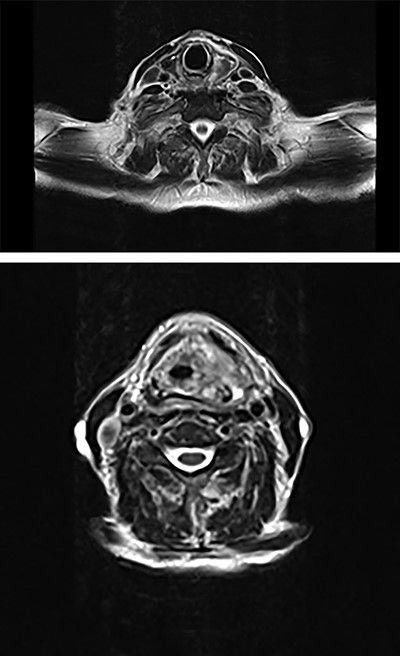

Full blood count, renal function and coagulation profile were within normal limits. C-Reactive protein was mildly raised at 73 mg/l. Neck axial contrast enhanced computer tomography (CT) scan was consistent with significant paraesophageal gas and mediastinitis (Fig. 1). Magnetic resonance imaging (MRI) suggested an enhancing collection from the left parapharyngeal space extending to the mediastinum (Fig. 2). Intravenous Fluconazole was added.

Axial plane MRI of neck and thorax showing a heterogenous collection on left parapharyngeal space extending inferiorly.